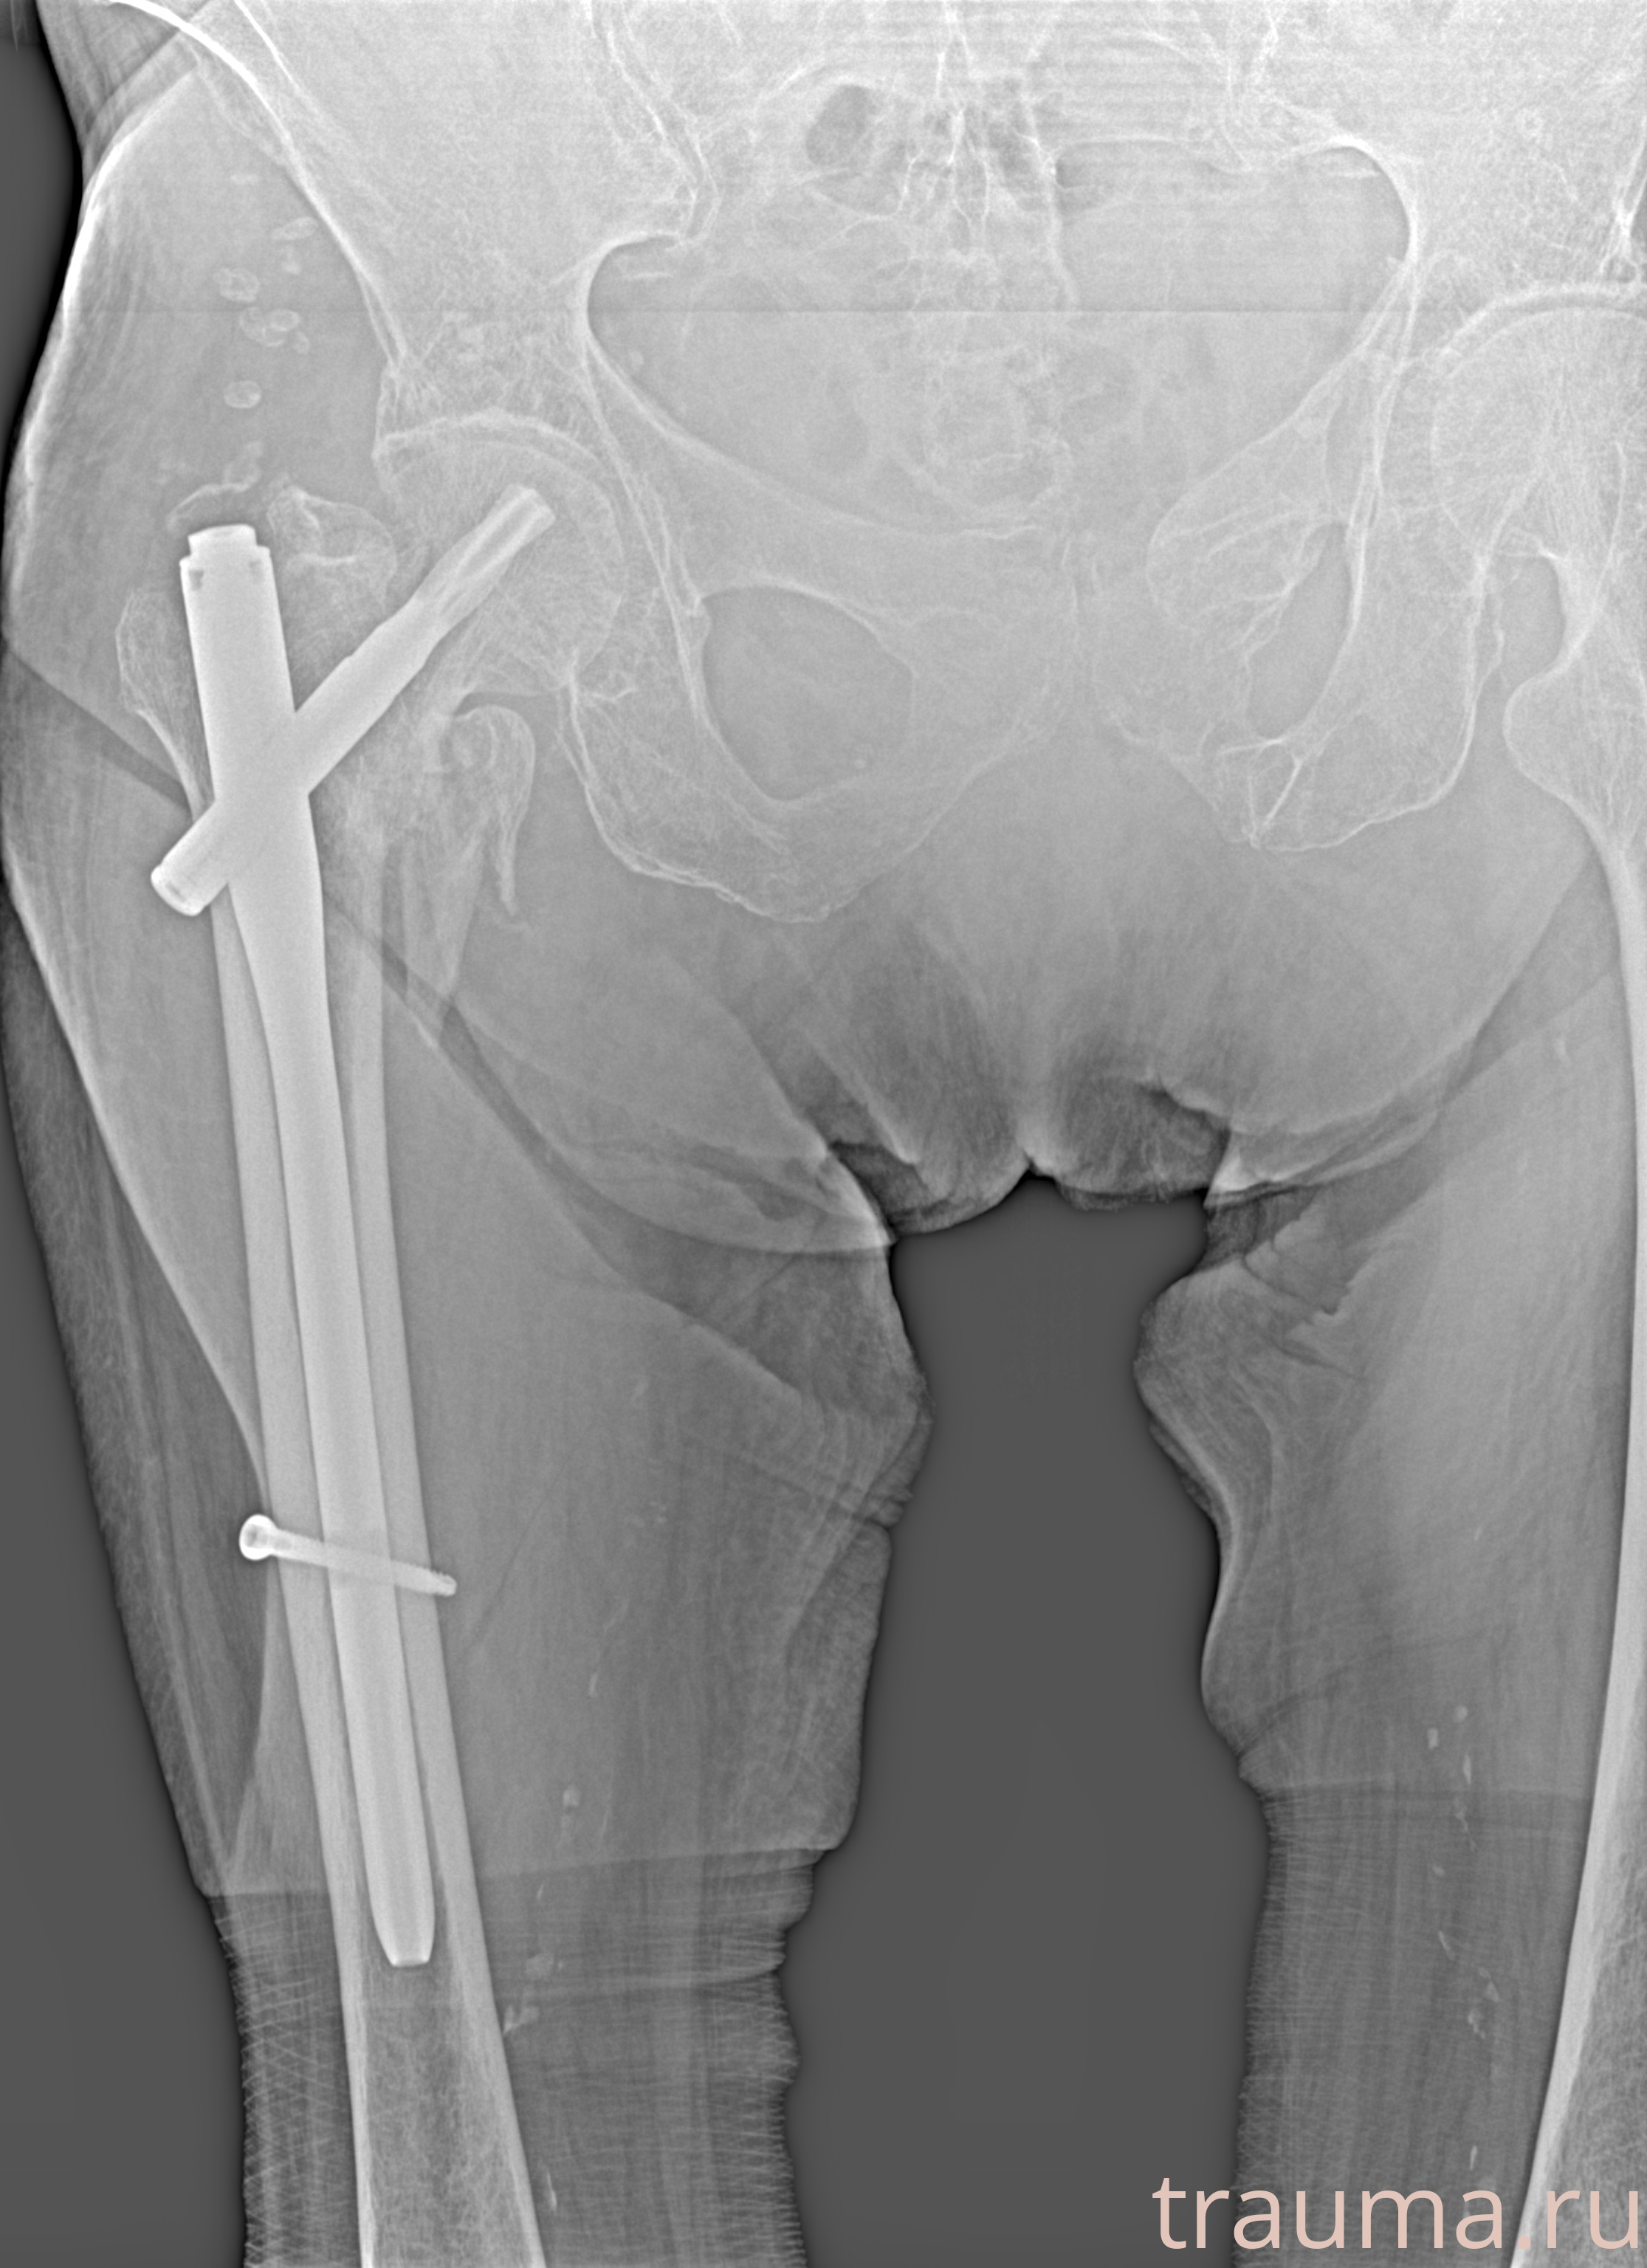

Рентген на дому: по вашему адресу приезжает врач-рентгенолог, травматолог-ортопед с мобильным рентгеновским аппаратом, проводит диагностику травмы или заболевания, делает необходимые рентгенограммы, дает рекомендации по дальнейшему лечению. Получить качественные снимки в домашних условиях возможно благодаря уникальной методике, разработанной МосРентген Центром для института  Склифосовского

при переломе шейки бедра и пневмонии от компании МосРентген Центр - партнера Института имени Склифосовского